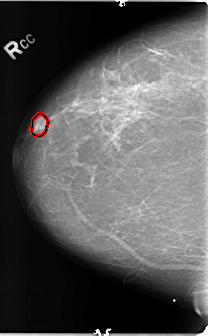

ics_version 1.0 filename B-3144-1 DATE_OF_STUDY 25 7 1997 PATIENT_AGE 43 FILM FILM_TYPE REGULAR DENSITY 2 DATE_DIGITIZED 5 5 1998 DIGITIZER LUMISYS LASER SEQUENCE LEFT_CC LINES 4832 PIXELS_PER_LINE 3080 BITS_PER_PIXEL 12 RESOLUTION 50 NON_OVERLAY LEFT_MLO LINES 4744 PIXELS_PER_LINE 3112 BITS_PER_PIXEL 12 RESOLUTION 50 NON_OVERLAY RIGHT_CC LINES 4704 PIXELS_PER_LINE 2904 BITS_PER_PIXEL 12 RESOLUTION 50 OVERLAY RIGHT_MLO LINES 4744 PIXELS_PER_LINE 3176 BITS_PER_PIXEL 12 RESOLUTION 50 OVERLAY |

FILE: B_3144_1.RIGHT_CC.OVERLAY TOTAL_ABNORMALITIES 1 ABNORMALITY 1 LESION_TYPE MASS SHAPE OVAL MARGINS CIRCUMSCRIBED-ILL_DEFINED ASSESSMENT 4 SUBTLETY 4 PATHOLOGY BENIGN TOTAL_OUTLINES 1 BOUNDARY |